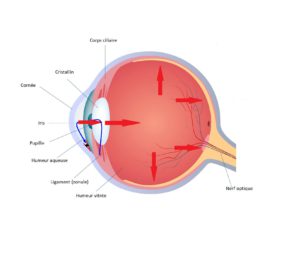

Le corps ciliaire situé juste en arrière de l’iris produit un liquide transparent nommé humeur aqueuse qui circule en avant du cristallin et de l’iris dans ce qui est appelé la chambre antérieure. L’évacuation de ce liquide se fait par l’angle irido cornéen (situé entre l’iris et la cornée) au travers d’un filtre nommé le trabéculum.

Il peut exister un obstacle au passage de l’humeur aqueuse lorsque l’iris est particulièrement dilaté (la nuit). On parle alors de glaucome par fermeture de l’angle.

Lorsqu’il n’y a aucun obstacle en amont du trabéculum mais que ce dernier présente une résistance anormalement importante au passage de l’humeur aqueuse, une élévation de la tension oculaire, apparait qui engendre le glaucome à angle ouvert.

Il existe deux grandes familles de collyres utilisés dans le traitement du glaucome : soit on diminue la sécrétion d’humeur aqueuse, soit on augmente l’évacuation de cette dernière